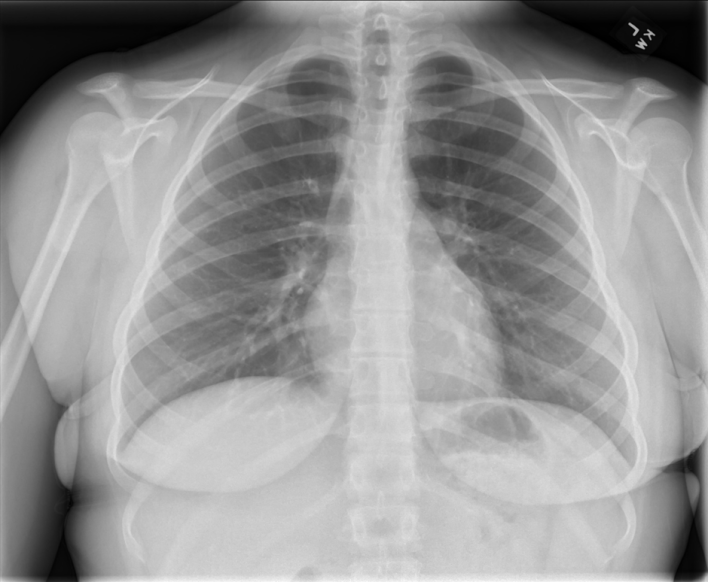

Next, check the cardiac size: normal is <50% of thoracic diameter on PA projection and <55% on AP projection.

Normal Cardiac Size on PA CXR

Red = thoracic diameter; Yellow = cardiac diameter